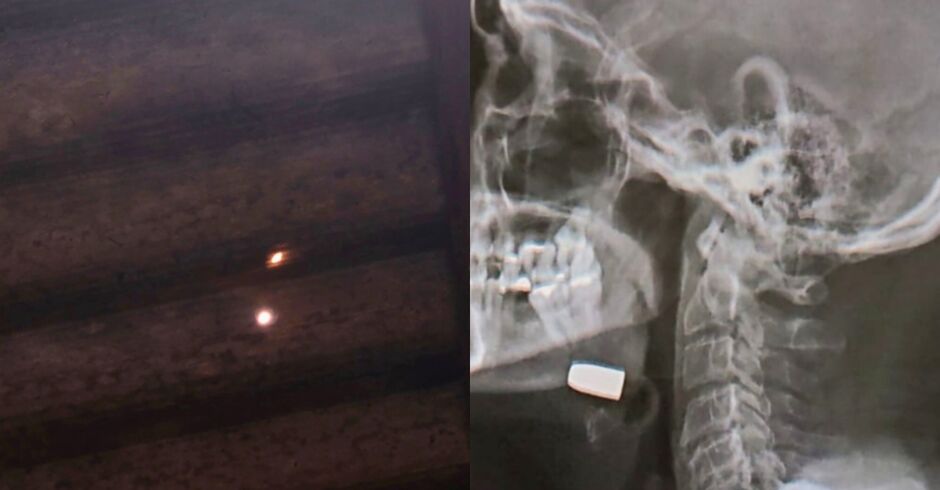

Homem de 58 anos foi atingido por uma bala perdida enquanto dormia em casa, no bairro São Bento, em Sidrolândia. O caso, registrado como lesão corporal dolosa, ocorreu na madrugada de sexta-feira (12), mas só foi confirmado na madrugada de domingo (14), após exames médicos.

Na noite de sábado (13), a vítima procurou o Hospital Beneficente Dona Elmíria Silvério Barbosa devido à piora no quadro, segundo o site Noticidade. Após a realização de exames de imagem, foi constatado que ele estava com um projétil alojado na região do rosto, sendo necessária intervenção cirúrgica para a retirada.

Ainda de acordo com a vítima, ele dormia em sua casa quando sentiu forte ardência e dor, mas não chegou a ouvir estampidos de disparo. Apenas no período da tarde de sábado (13) percebeu um buraco no teto de sua residência, possivelmente causado pelo projétil que o atingiu.